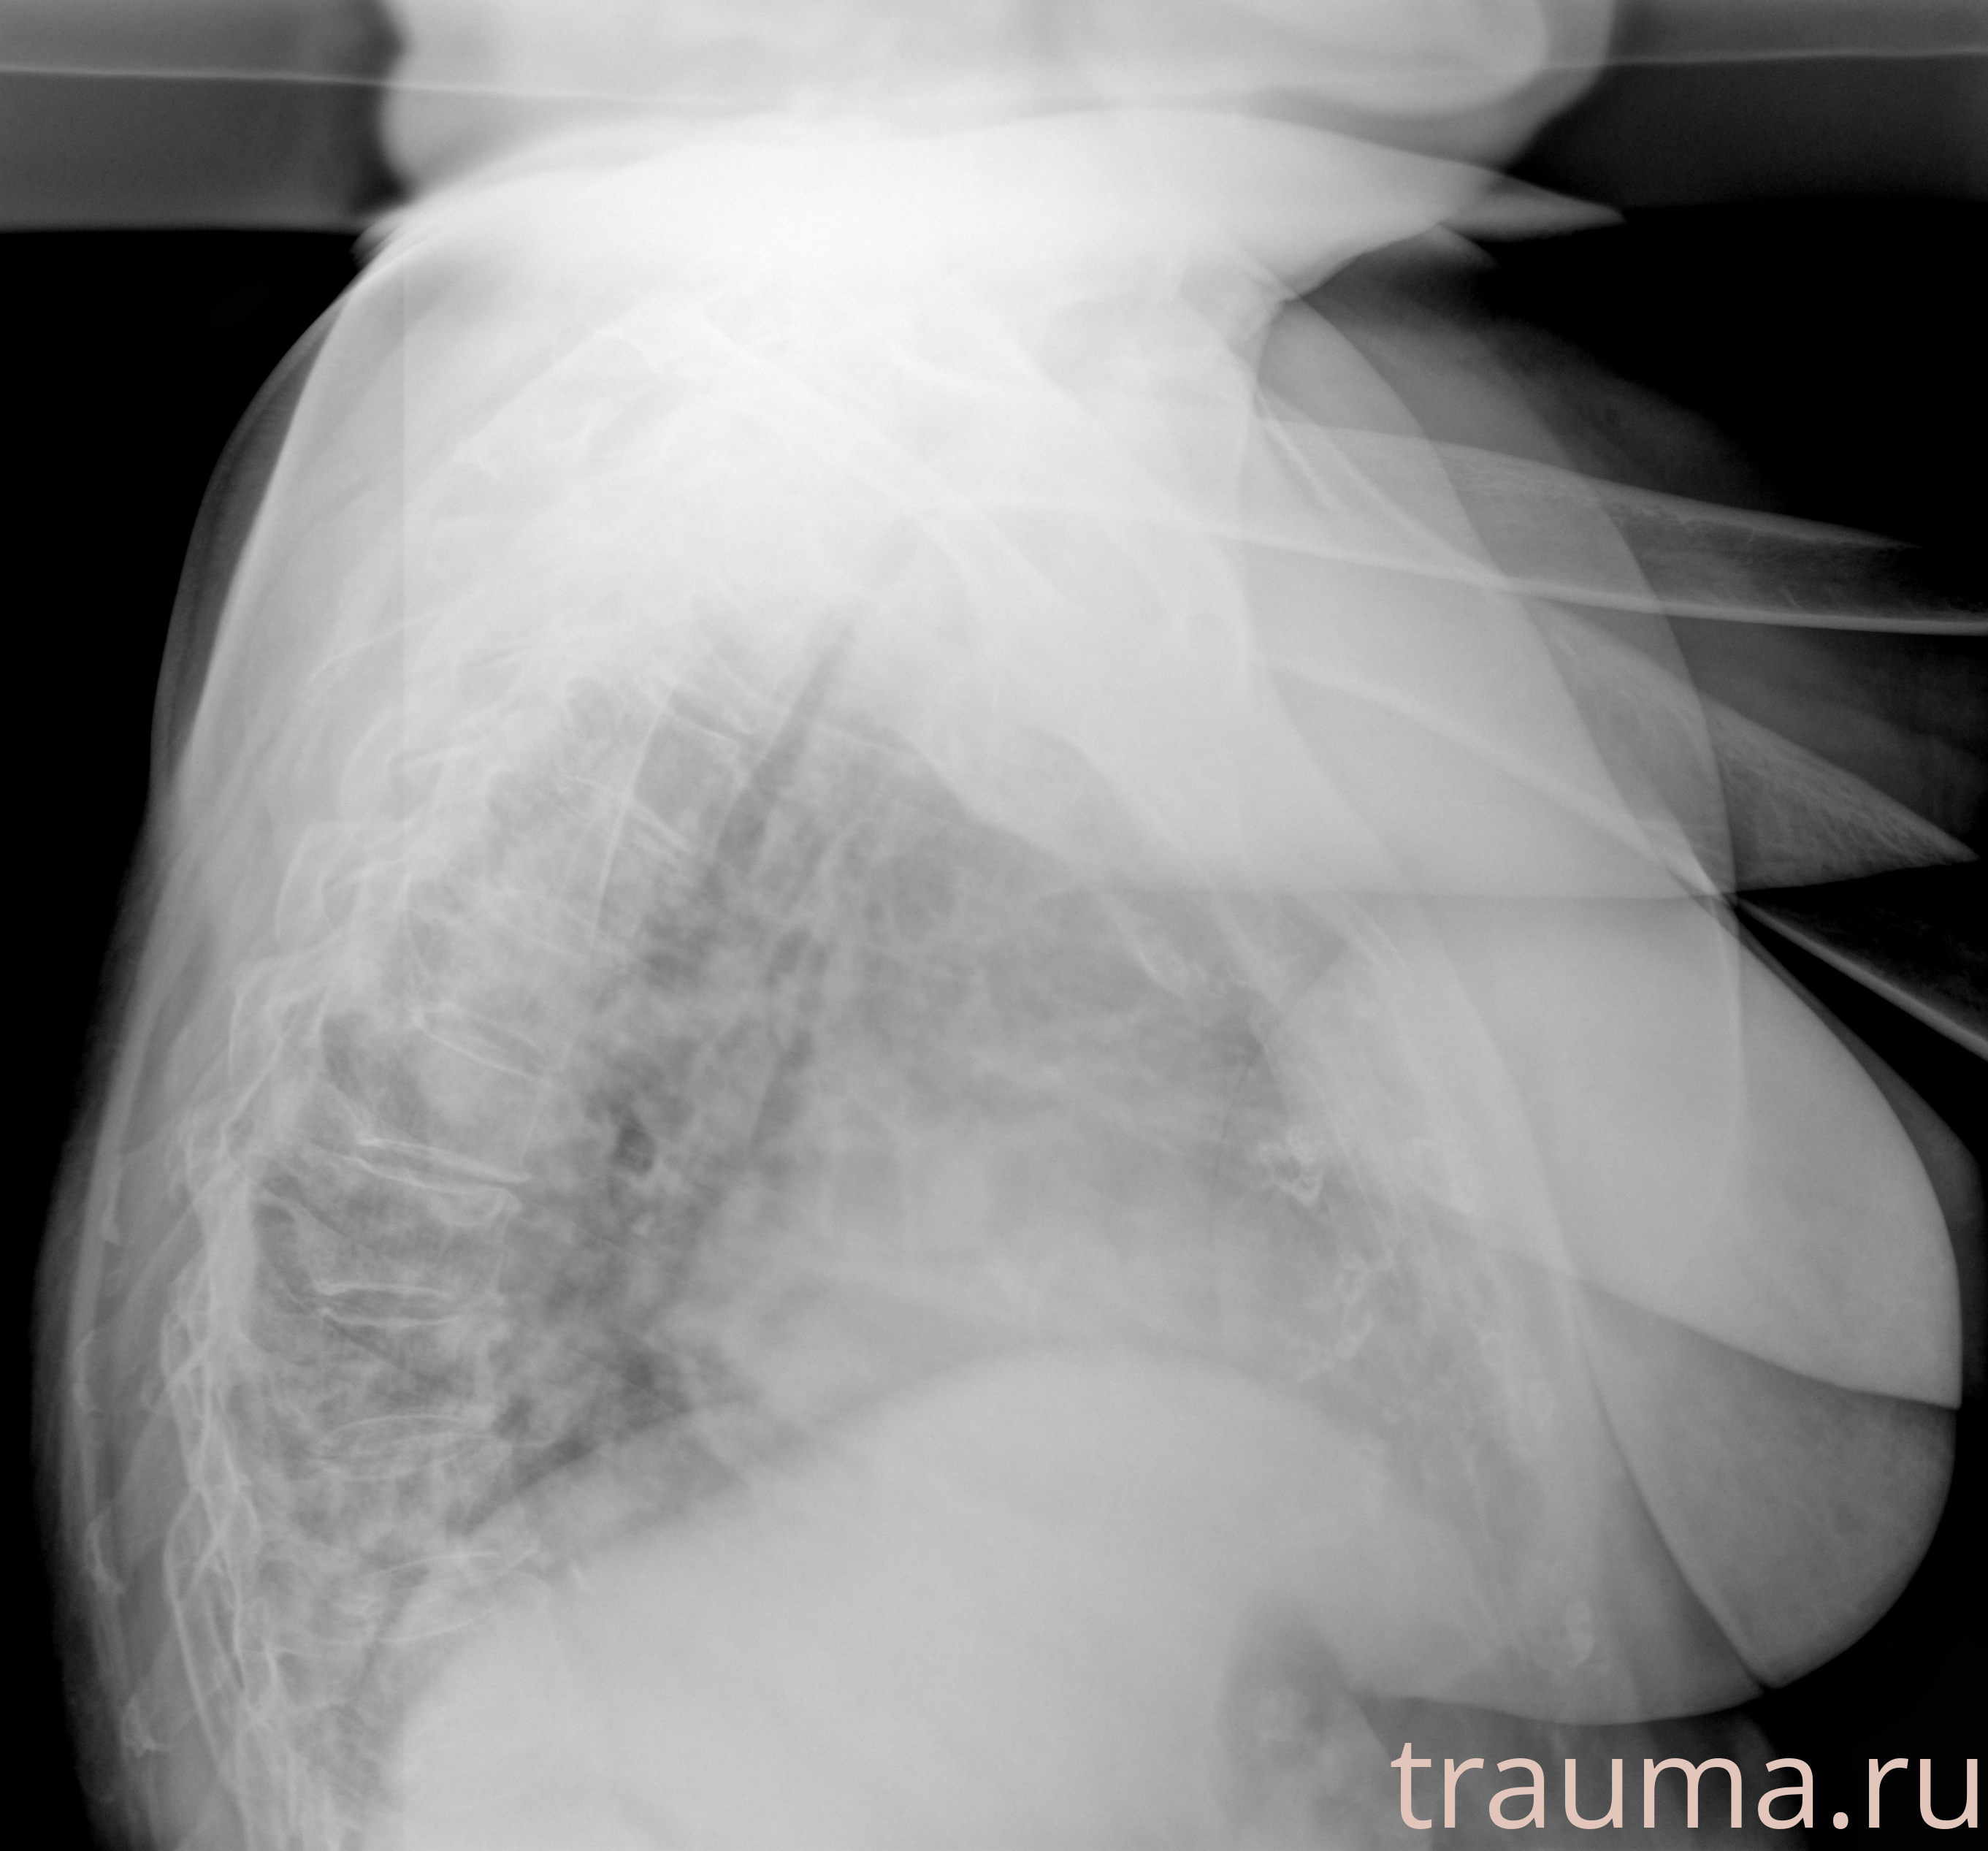

Рентген на дому: по вашему адресу приезжает врач-рентгенолог, травматолог-ортопед с мобильным рентгеновским аппаратом, проводит диагностику травмы или заболевания, делает необходимые рентгенограммы, дает рекомендации по дальнейшему лечению. Получить качественные снимки в домашних условиях возможно благодаря уникальной методике, разработанной МосРентген Центром для института  Склифосовского

при переломе шейки бедра и пневмонии от компании МосРентген Центр - партнера Института имени Склифосовского